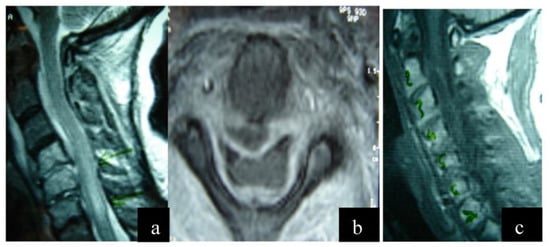

| 1 | 23 | M | C2–C4 | Staphylococcus aureus | Debridement and fusion | Fever, pain, numbness, and muscle weakness bilaterally | Full recovery, dysphagia for 2 weeks postop | Abuse of venous drugs |

| 2 | 68 | M | C2–C4 | Staphylococcus aureus | Debridement and fusion | Fever, pain, numbness, and muscle weakness bilaterally | Full recovery | Diabetes mellitus |

| 3 | 56 | F | C1–C5 | Staphylococcus aureus | Debridement and fusion | Fever, pain, numbness, and muscle weakness bilaterally | Full recovery 2 years post op, muscle weakness | |

| 4 | 69 | M | C2–C5 | Staphylococcus aureus | Debridement and fusion | Incidentally upon spinal imaging | Full recovery, dysphagia for 2 weeks postop |